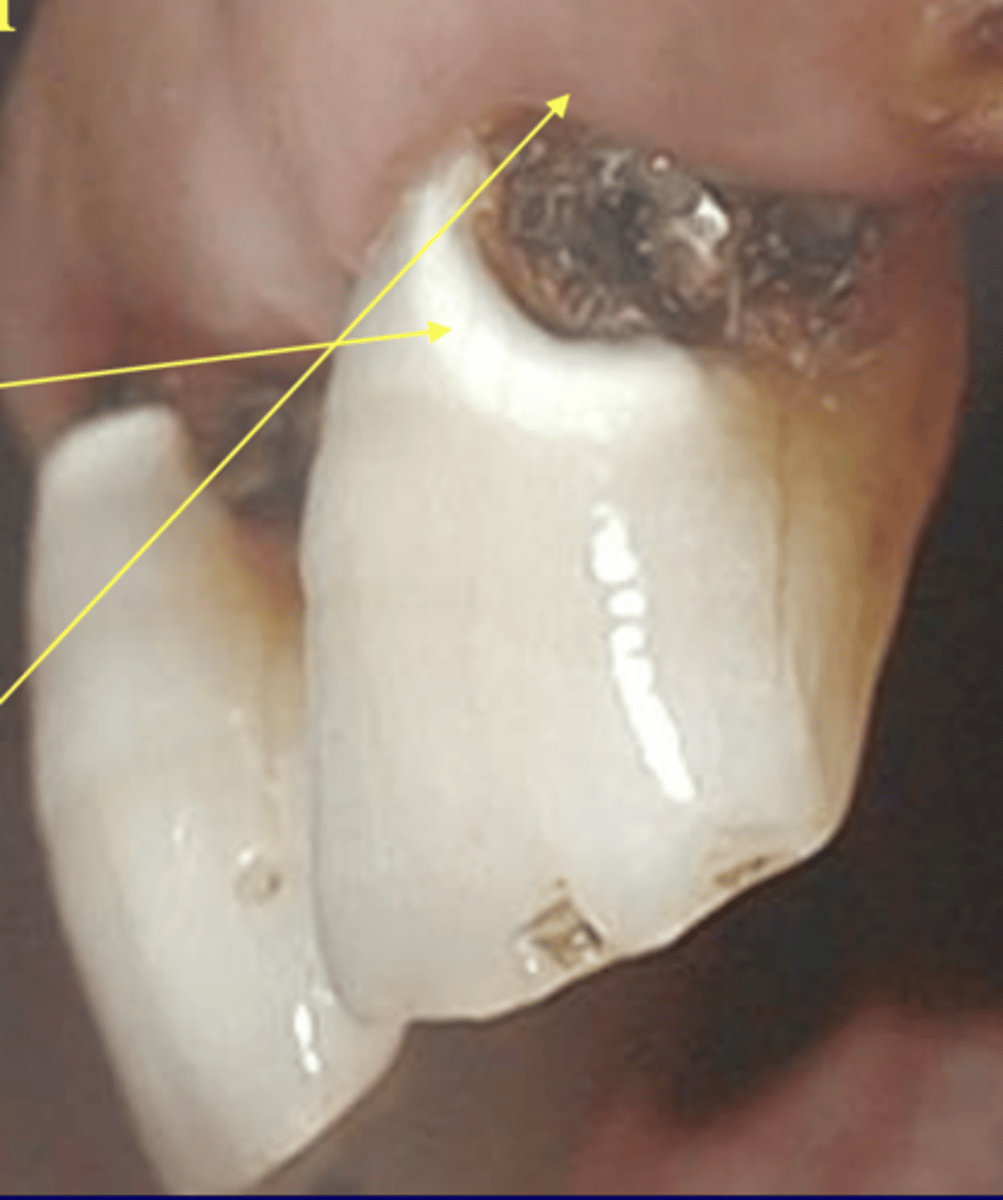

Where are class 5 caries detected?

gingival third of buccal or lingual surfaces

True / False: a halo indicates extensive decay

True

In class 5 caries, decay frequently extends ---- creating an access problem

subgnigivally